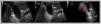

Abdominal ultrasound. (A) Inflammatory-oedematous changes in gallbladder wall with diffuse wall thickening (white arrows). (B) Marked increase in blood flow on Doppler (white arrow). (C) Visualization of spots in the gallbladder compatible with biliary sludge (white arrow) and oedema of surrounding fat tissue (red arrow).

The patient was a boy aged 9 years with CF who carried the N1303K/R334W variants, without pancreatic insufficiency, with a history of chronic cough of 2 years’ duration and mild to moderate pulmonary exacerbations and detection of Staphylococcus aureus in throat swab specimens. He was managed with nebulised 3% hypertonic saline solution, oral azithromycin given 3 days a week and chest physiotherapy. The forced spirometry assessment was normal, with a forced expiratory volume in 1 second (FEV1) of 1.92 L (z score of −0.7 in relation to the reference group). The computed tomography of the lungs showed generalised cylindrical bronchiectasis, mucus plugging, involvement of small-calibre bronchi with mosaic attenuation and a Bhalla score of 15 (threshold of normal: 25). At the gastrointestinal level, the patient had adequate pancreatic function and growth (52nd percentile for weight and 83rd for height), but there was evidence of hepatobiliary involvement in the abdominal ultrasound (gallbladder sludge), managed with ursodeoxycholic acid. Due to progressive clinical and radiological pulmonary worsening in the last 3 years, the decision was made to initiate ETI therapy based on recently published articles that reported a favourable response in vitro and in patients carrying the N1303K variant, as did ours. The patient was given the adult dose for more than 30 kg of body weight (2 tablets containing 75 mg of ivacaftor, 50 mg of tezacaftor and 100 mg of elexacaftor in the morning and 1 tablet containing 150 mg de ivacaftor at night). Six days after starting treatment, the patient reported colicky abdominal pain in the right hypochondrium and epigastrium. The patient had no fever, choluria, vomiting or diarrhoea. In the physical examination, the skin colour was normal, and the patient experienced pain on palpation of the right hypochondrium with a positive Murphy sign. The abdominal ultrasound showed multiple hyperechoic spots suggestive of biliary sludge in the gallbladder; inflammatory changes and oedema of the gallbladder wall, with diffuse wall thickening and markedly increased blood flow on Doppler, along with inflammatory changes in the adjacent adipose tissue (Fig. 1), while all other organs, including the pancreas, had a normal appearance. Laboratory tests revealed levels of C-reactive protein, procalcitonin, white blood cells, pancreatic lipase, transaminases and bilirubin in the normal range. Given the findings compatible with acute cholecystitis, ETI was discontinued and analgesia provided to the patient, which achieved resolution of symptoms within 48 hours. Two months later, a follow-up abdominal ultrasound evinced resolution of the inflammatory process, and treatment with ETI was reintroduced in gradually increasing doses. Eventually, the indicated dose for the patient’s weight was reached and could be maintained without additional adverse events. Table 1 summarises the changes observed at 8 weeks of treatment, the most salient of which was a 24 mEq/L decrease in sweat chloride.